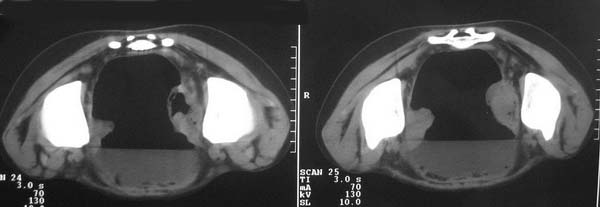

直肠左侧低密度模糊影,乙状结肠明显扩张,有宽大液平,下腹部肠袢欠规整,内有多发小液平,结合有阑尾炎手术史考虑:直肠周围脓肿,低位肠梗阻,肠粘连。

盆腔巨大脓肿,据术者讲,脓肿大部分壁是有肠管壁形成的,少部分有自己较厚的壁,子宫、附件都泡在脓液里,腹腔肠管广泛粘连,这个病例奇怪的是急性发病,追问不出慢性病史。

考虑:肠粘连并低位肠梗阻;乙状结肠与回肠之间形成肠篓

结果收到,谢谢楼主,对照结果,回过头看,乙状结肠后壁液性低密度影应该也是脓肿。